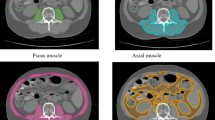

Pre-surgical abdominal CT images were used for evaluation of total psoas muscle area and density. CT scans (5 mm collimation width) were performed using a GE LightSpeed 64-slice multidetector helical CT scanner (GE Healthcare Japan Corporation, Tokyo, Japan) and scanned images were analyzed on a GE workstation by one well-trained radiologist, blinded to patient outcomes, at each institution. A digital free-hand outline of the left and right psoas muscles was made on the axial non-contrast CT image at level L3 (Fig. 5). By this procedure, the area in cm2 and density in HU of each psoas muscle at this level were automatically calculated. To assess sarcopenia, PMI in cm2/m2 was calculated by normalizing the total psoas muscle area (left and right psoas muscle area) by the square of the patient’s height7. To assess myosteatosis, ATPD in HU was also calculated as an average of left and right psoas muscle density20.